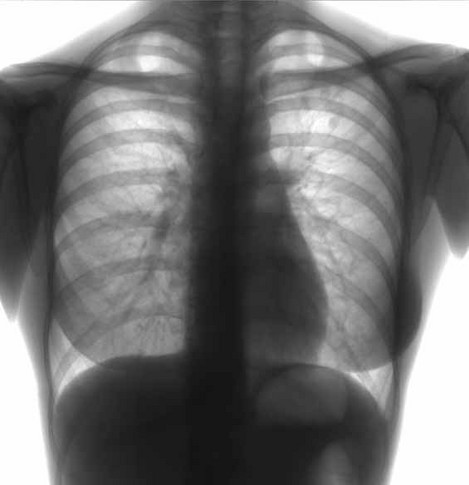

| Здоровье ваших легких лёгкие чем можно очистить лёгкие бег помогает |

Почему важно чистить легкие. |